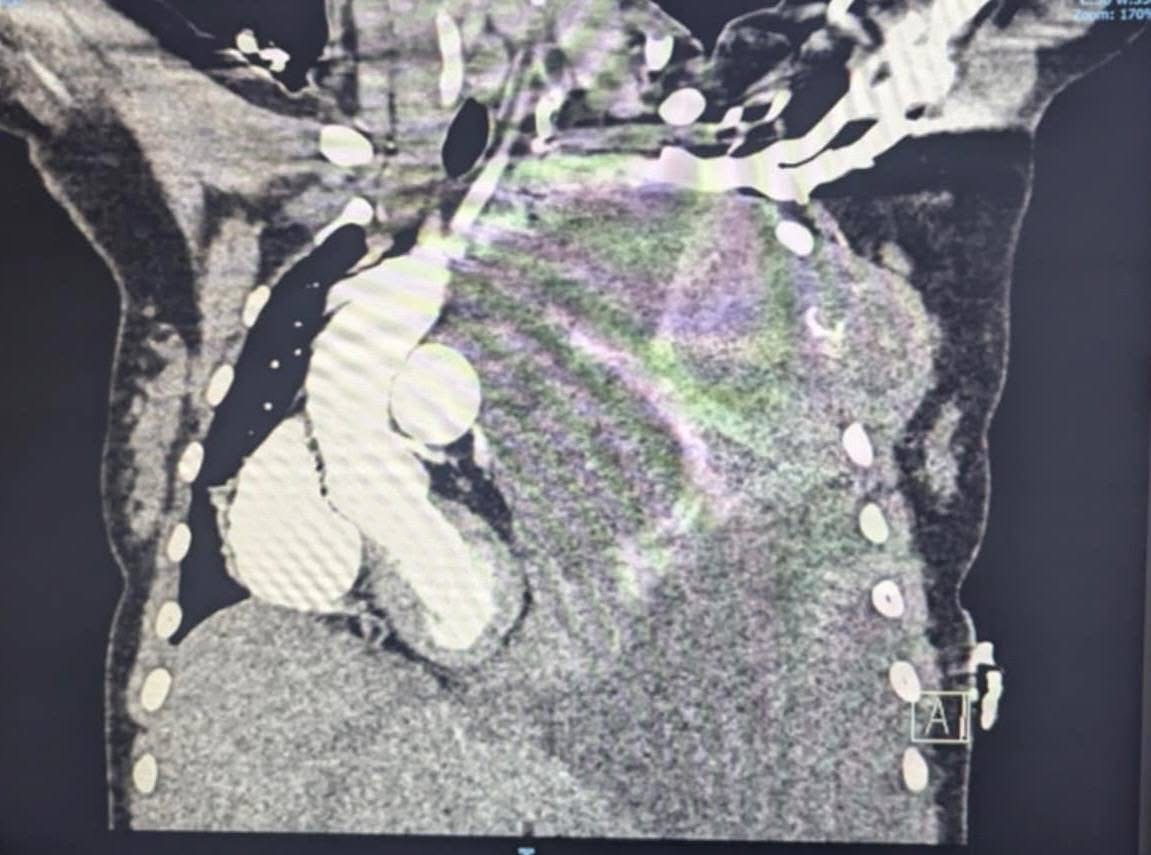

A tragic update has been shared on the campaign to help Chrissy and her family. The cancer, diagnosed as stage 4 undifferentiated round cell sarcoma, is now rapidly spreading, and her condition is deteriorating. Doctors have added multifocal osseous metastatic disease to her diagnosis, noting a massive tumor in her lungs and cancer in her pelvis and multiple vertebrae (T6, T7, T8, T9, and T12) of her spine.

Okay yall things are starting to get a little more serious with moma. Just look at the change in just these few months. The Send Moma A Dollar Campaign is officially starting. Our original goal was $50,000 and started as a joke. But have raised over $1202. We have actually found a place that moma really wants and is move in ready. Please please please share this post.

On March 18, 2025, while she was pregnant, Chrissy, at just 29 years old, was diagnosed with stage 4 round cell undifferentiated sarcoma. This aggressive cancer shattered their world, turning their hopes for a future home into a desperate fight for survival. The fight began almost immediately. Baby Axel was born and spent 84 agonizing days in the NICU, while Chrissy began the relentless, exhausting cycle of treatments, hospital stays, and doctors' visits.